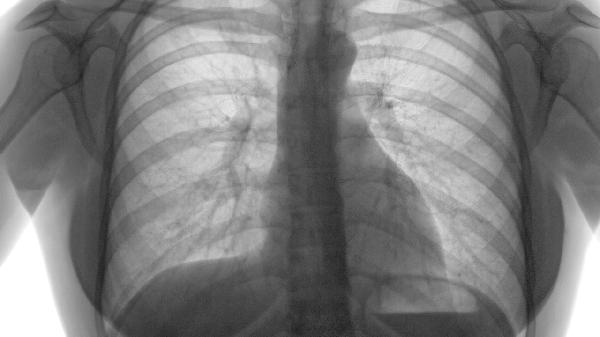

慢性肺气肿患者可遵医嘱使用布地奈德福莫特罗粉吸入剂、沙美特罗替卡松粉吸入剂、噻托溴铵粉吸入剂、氨茶碱片、乙酰半胱氨酸颗粒等药物减少发作。慢性肺气肿通常与长期吸烟、空气污染、遗传因素等有关,主要表现为活动后气促、慢性咳嗽等症状。